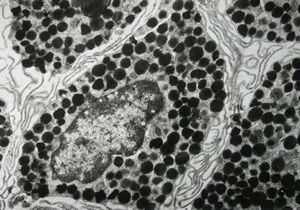

F, 24y. | molluscum contagiosum … virions

F, 24y. | molluscum contagiosum

F, 24y. | molluscum contagiosum

F, 7y. | molluscum contagiosum … virions

F, 7y. | molluscum contagiosum … virions

F, 24y. | molluscum contagiosum … virions